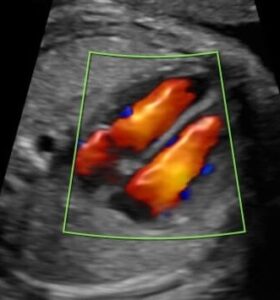

Στο κέντρο μας διενεργείται ο πλήρης υπερηχογραφικός έλεγχος που μπορεί να απαιτηθεί κατά τη διάρκεια της κύησης καθώς και επεμβατικός έλεγχος με βιοψία χοριακών λαχνών και αμνιοπαρακέντηση.

Όλες οι υπερηχογραφικές και επεμβατικές εξετάσεις πραγματοποιούνται σε ένα φιλικό και ήρεμο περιβάλλον με εξοπλισμό τελευταίας τεχνολογίας.